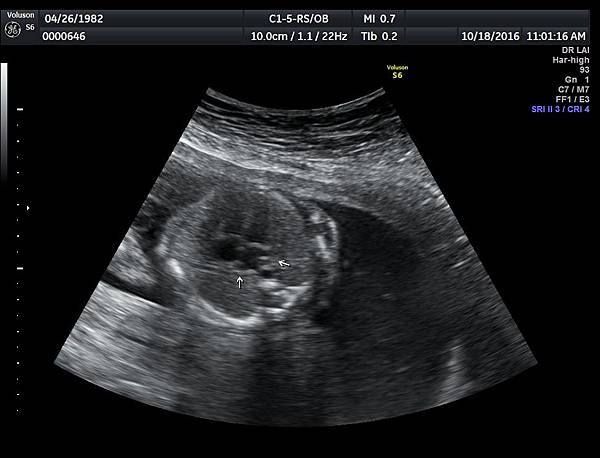

我看肺靜脈的心路歷程可以分成三個階段,第一個階段是用gray scale(黑白)看到左右肺靜脈下行支回到左心房(附圖 1.2.),第二個階段是用flow(彩色)看到左右肺靜脈回到左心房(附圖 3.4.),第三階段是同時要看到黑白和彩色的左右肺靜脈回到左心房,為什麼只有看flow(彩色)不安全呢?因為右肺靜脈的flow有時候是假影,為何會看到假影?因為右心房到左心房的flow overlapping(重疊)造成的(附圖 5.),如何判斷是假影,只要關掉flow看黑白的即可證明右肺靜脈沒有進入左心房(附圖 6.)。

如果同時看到左右肺靜脈進入左心房,這種誤判的機率下降很多,如果只能看到一條肺靜脈的血流,我會選擇左肺靜脈(附圖 7.8.),因為左肺靜脈的血流比較不會被overlapping,最安全的方法是黑白和彩色都看到左右肺靜脈進入左心房,只是需要胎兒姿勢配合,當然孕婦的體重也是需要考量的因素。